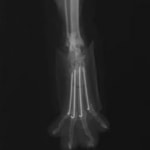

症例3:キルシュナーワイヤーのピンニングによる整復

ペルシャ猫 11ヶ月齢 雄

他院にて左大腿骨遠位の成長板骨折(salter-harrisⅠ型)が認められており、治療相談を目的として来院。当院にて、キルシュナーワイヤーを用いたピンニングにより骨折部位の整復を行いました。術後の経過は良好で、現在も経過観察中です。

術後レントゲン

機器

Arthrex社のターゲティングデバイスを用いてピンニングの位置を調整することで、確実な固定を行っています。当院ではこの手術器具以外にも、人の手術にも使用される様々な器具を導入し、手術精度を高め、また医療メーカーと新しい器具の開発、試作にも取り組んでおります。